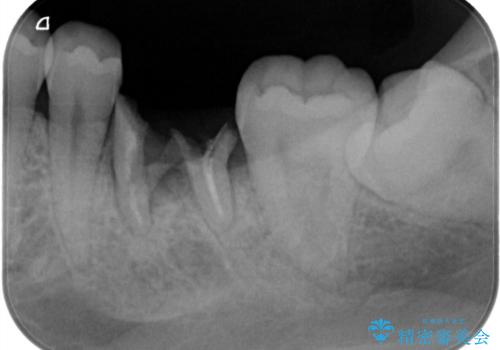

- 検査の結果、虫歯が見つかった患者様です。

白く目立たないものでの治療をご希望されたため、セラミックインレーでの治療となりました。

適合の良いセラミックインレーで修復することで見た目の綺麗さを保ったまま治療することができます。